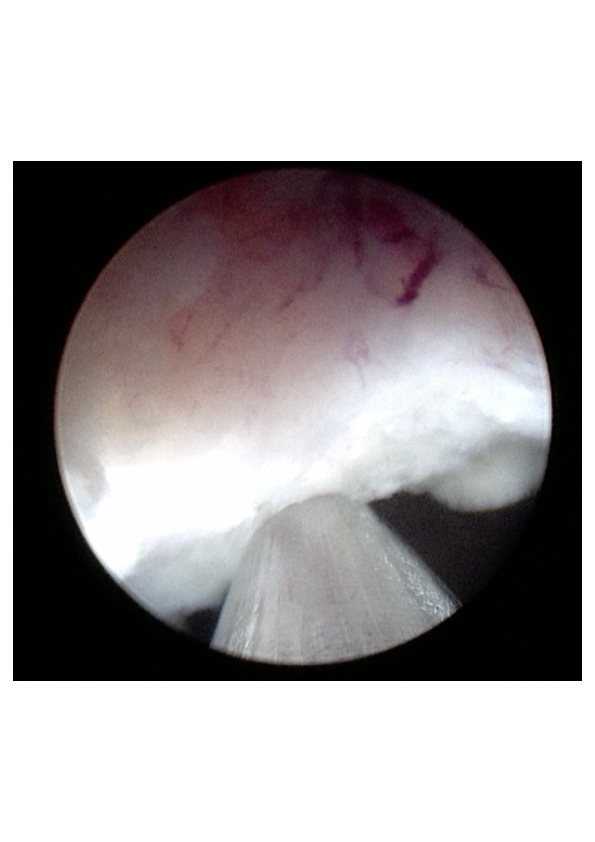

- το αδένωμα έχει πλέον αποκολληθεί από την προστατική κάψα και προωθείται στην ουροδόχο κύστη (εικόνες 5-6)

εικόνες 5-6